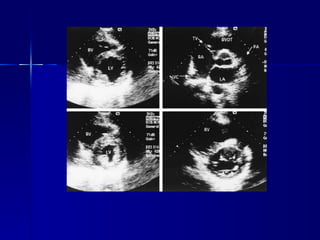

El ecocardiograma es un estudio no invasivo que utiliza ultrasonido para diagnosticar enfermedades cardíacas como valvulopatías, miocardiopatías y tumores. Ofrece modalidades como bidimensional, Doppler y tridimensional para evaluar estructuras del corazón. Es útil para cuantificar la gravedad de afecciones cardíacas y guiar el tratamiento. En el futuro podría usarse también como herramienta terapéutica.